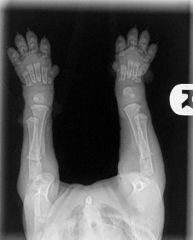

Un peu d'histoire: il s'agit d'un bébé chiot (nouveau-né) qui a eu un coup au coude et ne l'a pas utilisé correctement, il a donc été emmené chez le vétérinaire. Il n'y a rien de mal dans ces radiographies, heureusement, c'était une blessure aux tissus mous et il devrait être en bonne santé.